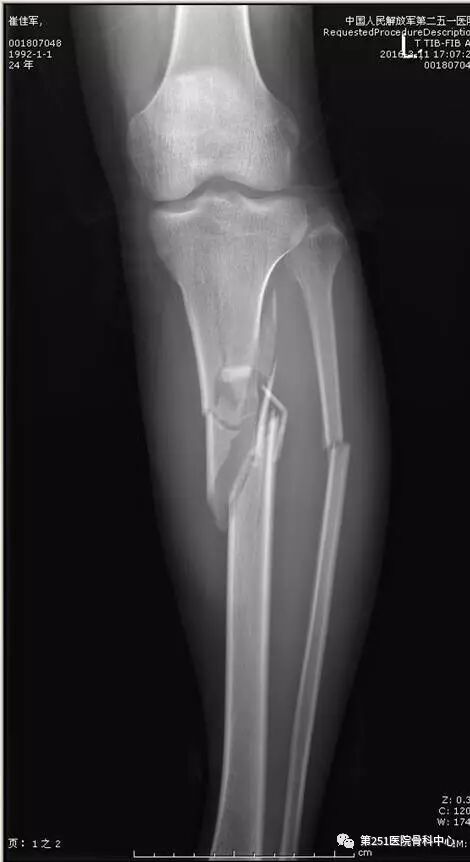

病例8:男性,24岁,车祸伤,胫腓骨近段粉碎性骨折。

![]()